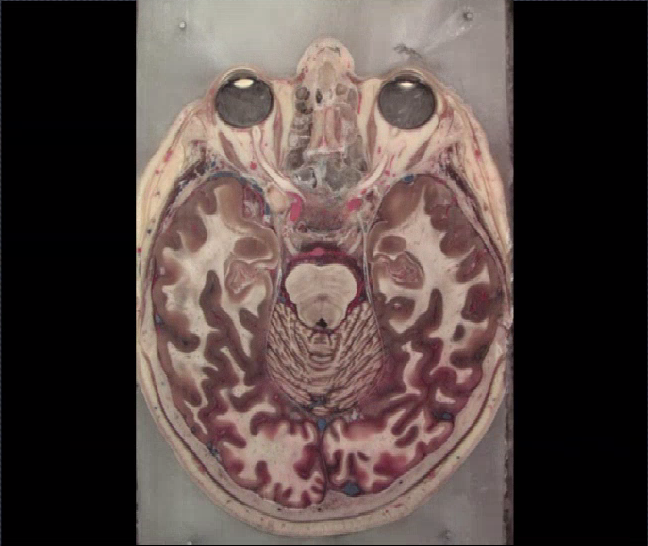

Caudal Pons

Rostral Medulla

Caudal medulla

Middle Pons

Rostral Pons

Caudal Midbrain

Rostral Midbrain